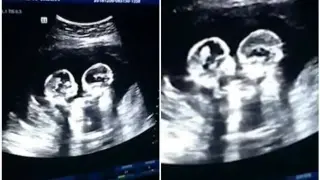

Една от любимите двойки на зрителите на "Един за друг" сподели радостна новина – очакват близнаци....